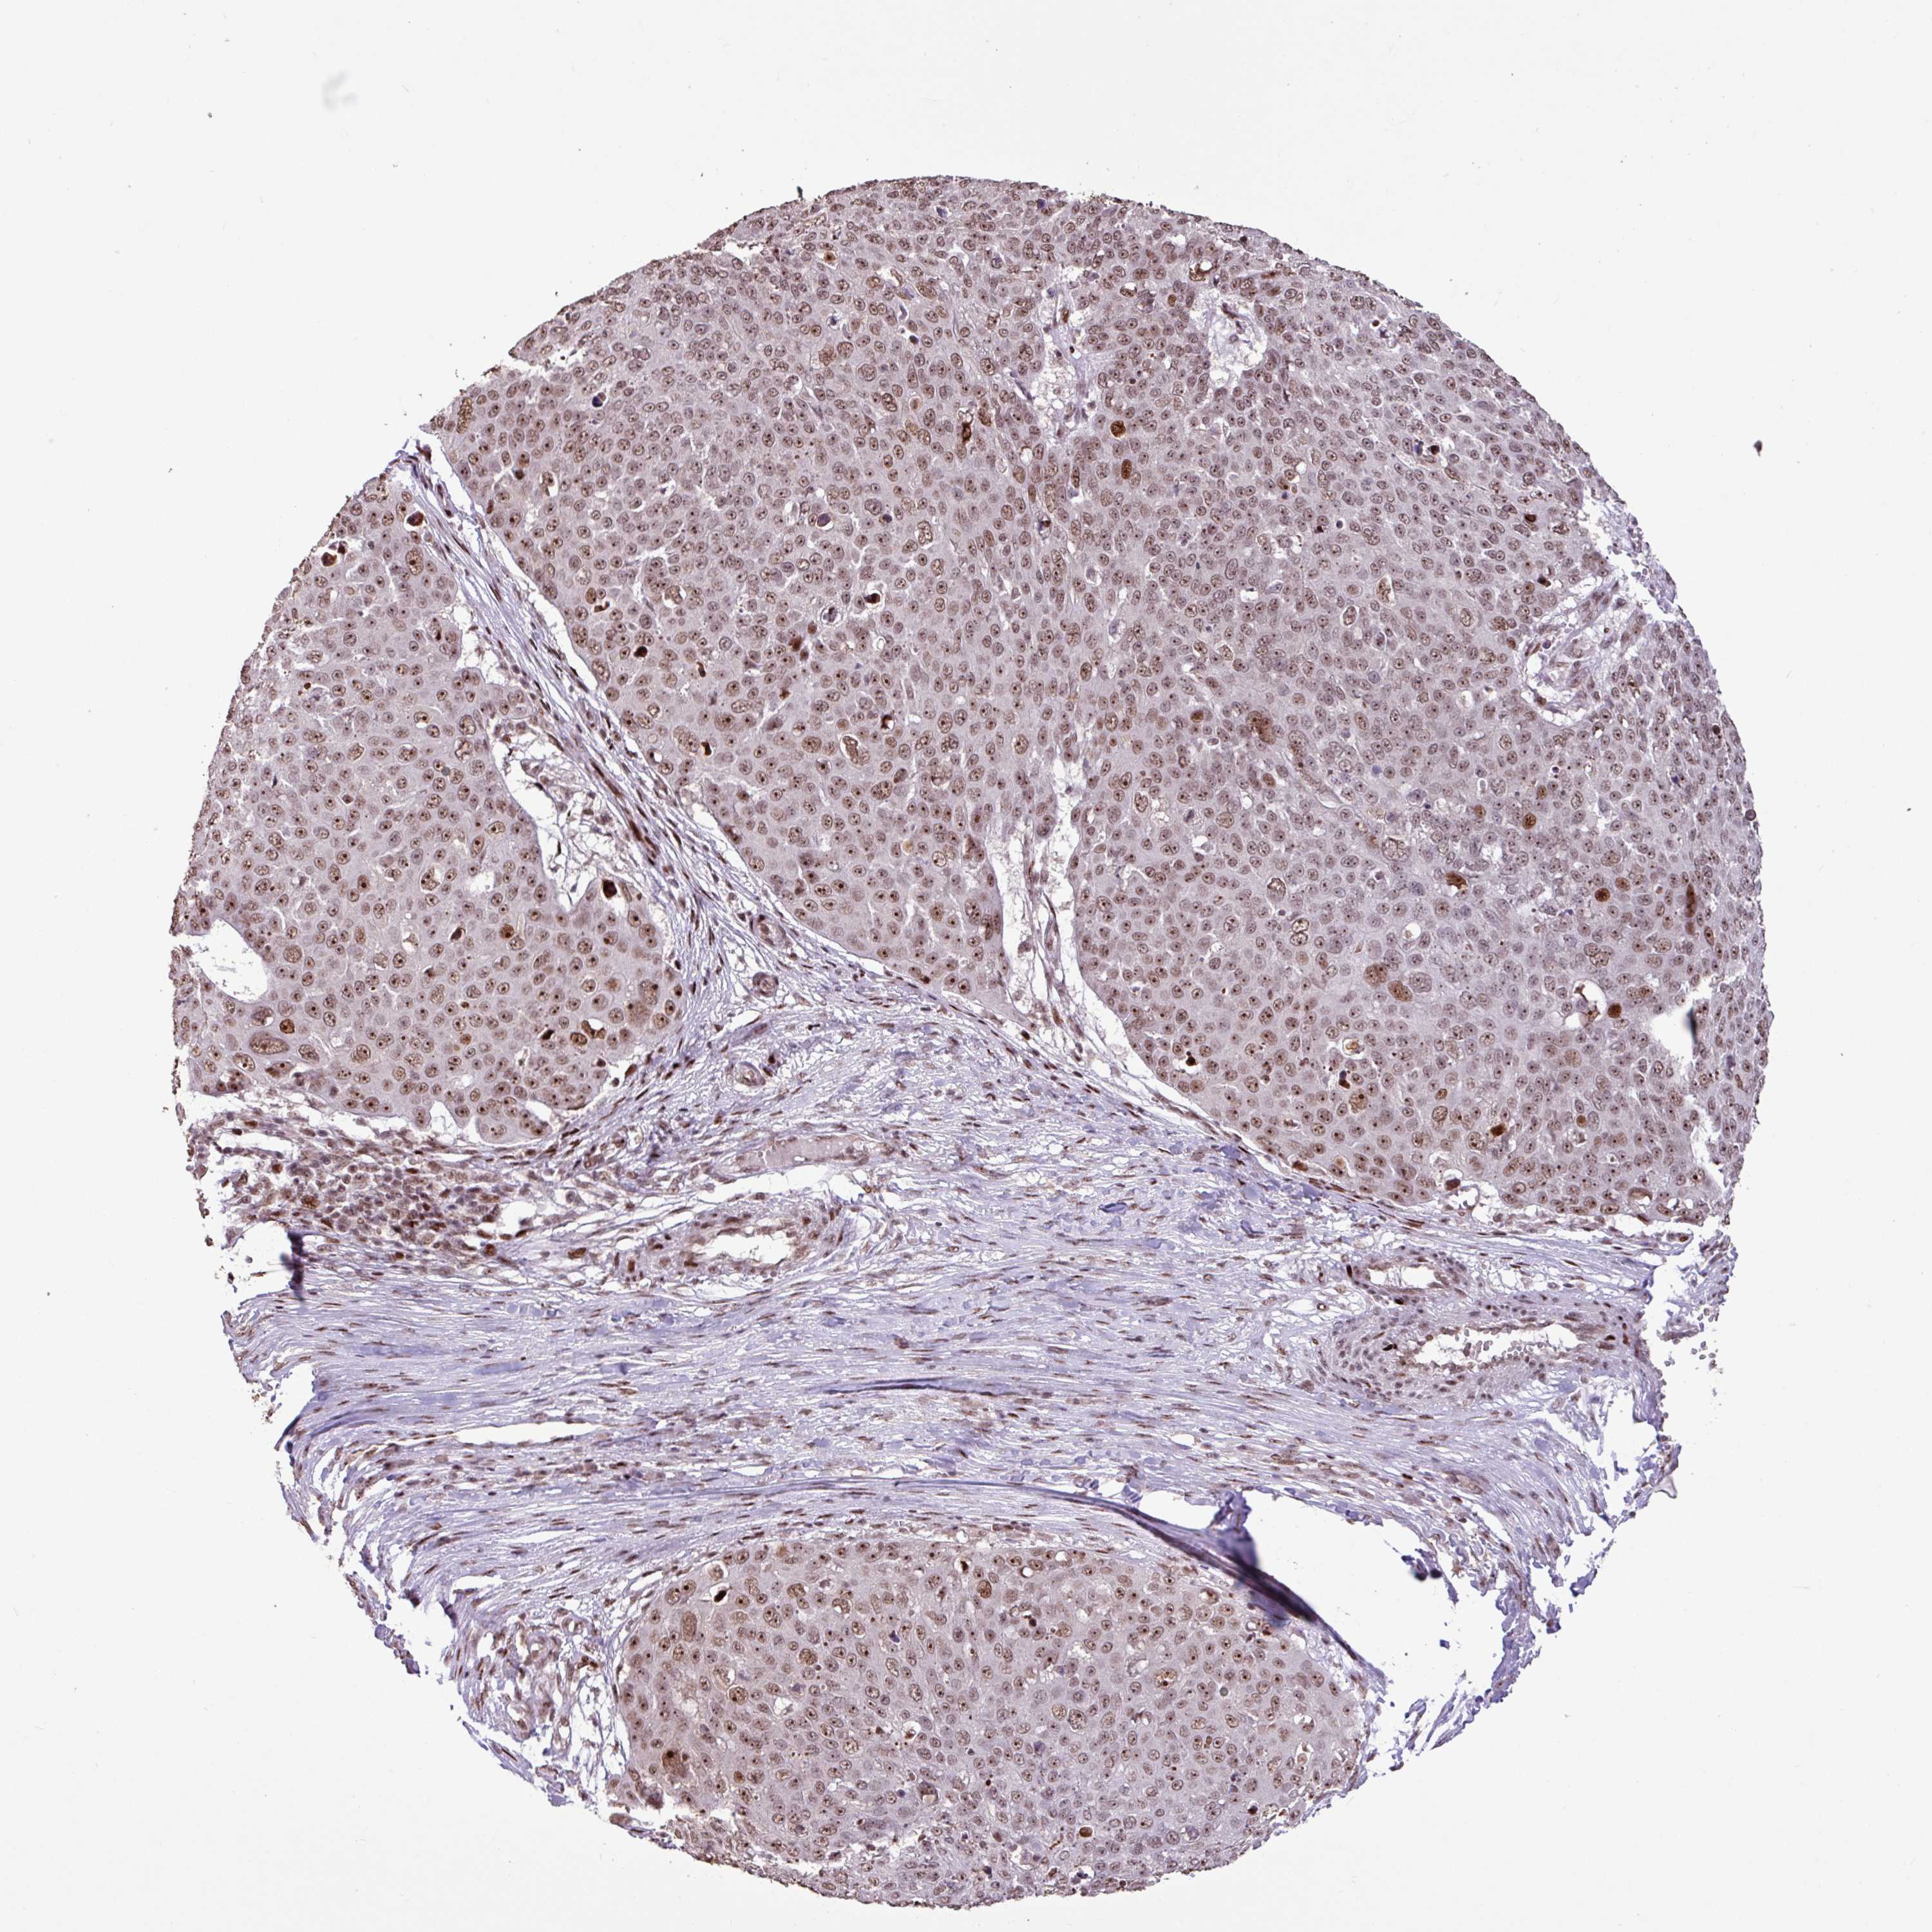

Basal cell and squamous cell cancer

SKIN CANCER - Protein expressioni

A mouse-over function shows sample information and annotation data. Click on an image to view it in a full screen mode. Samples can be filtered based on level of antibody staining by selecting one or several of the following categories: high, medium, low and not detected. The assay and annotation is described here.

Antibody HPA053153

Squamous cell carcinoma, NOS